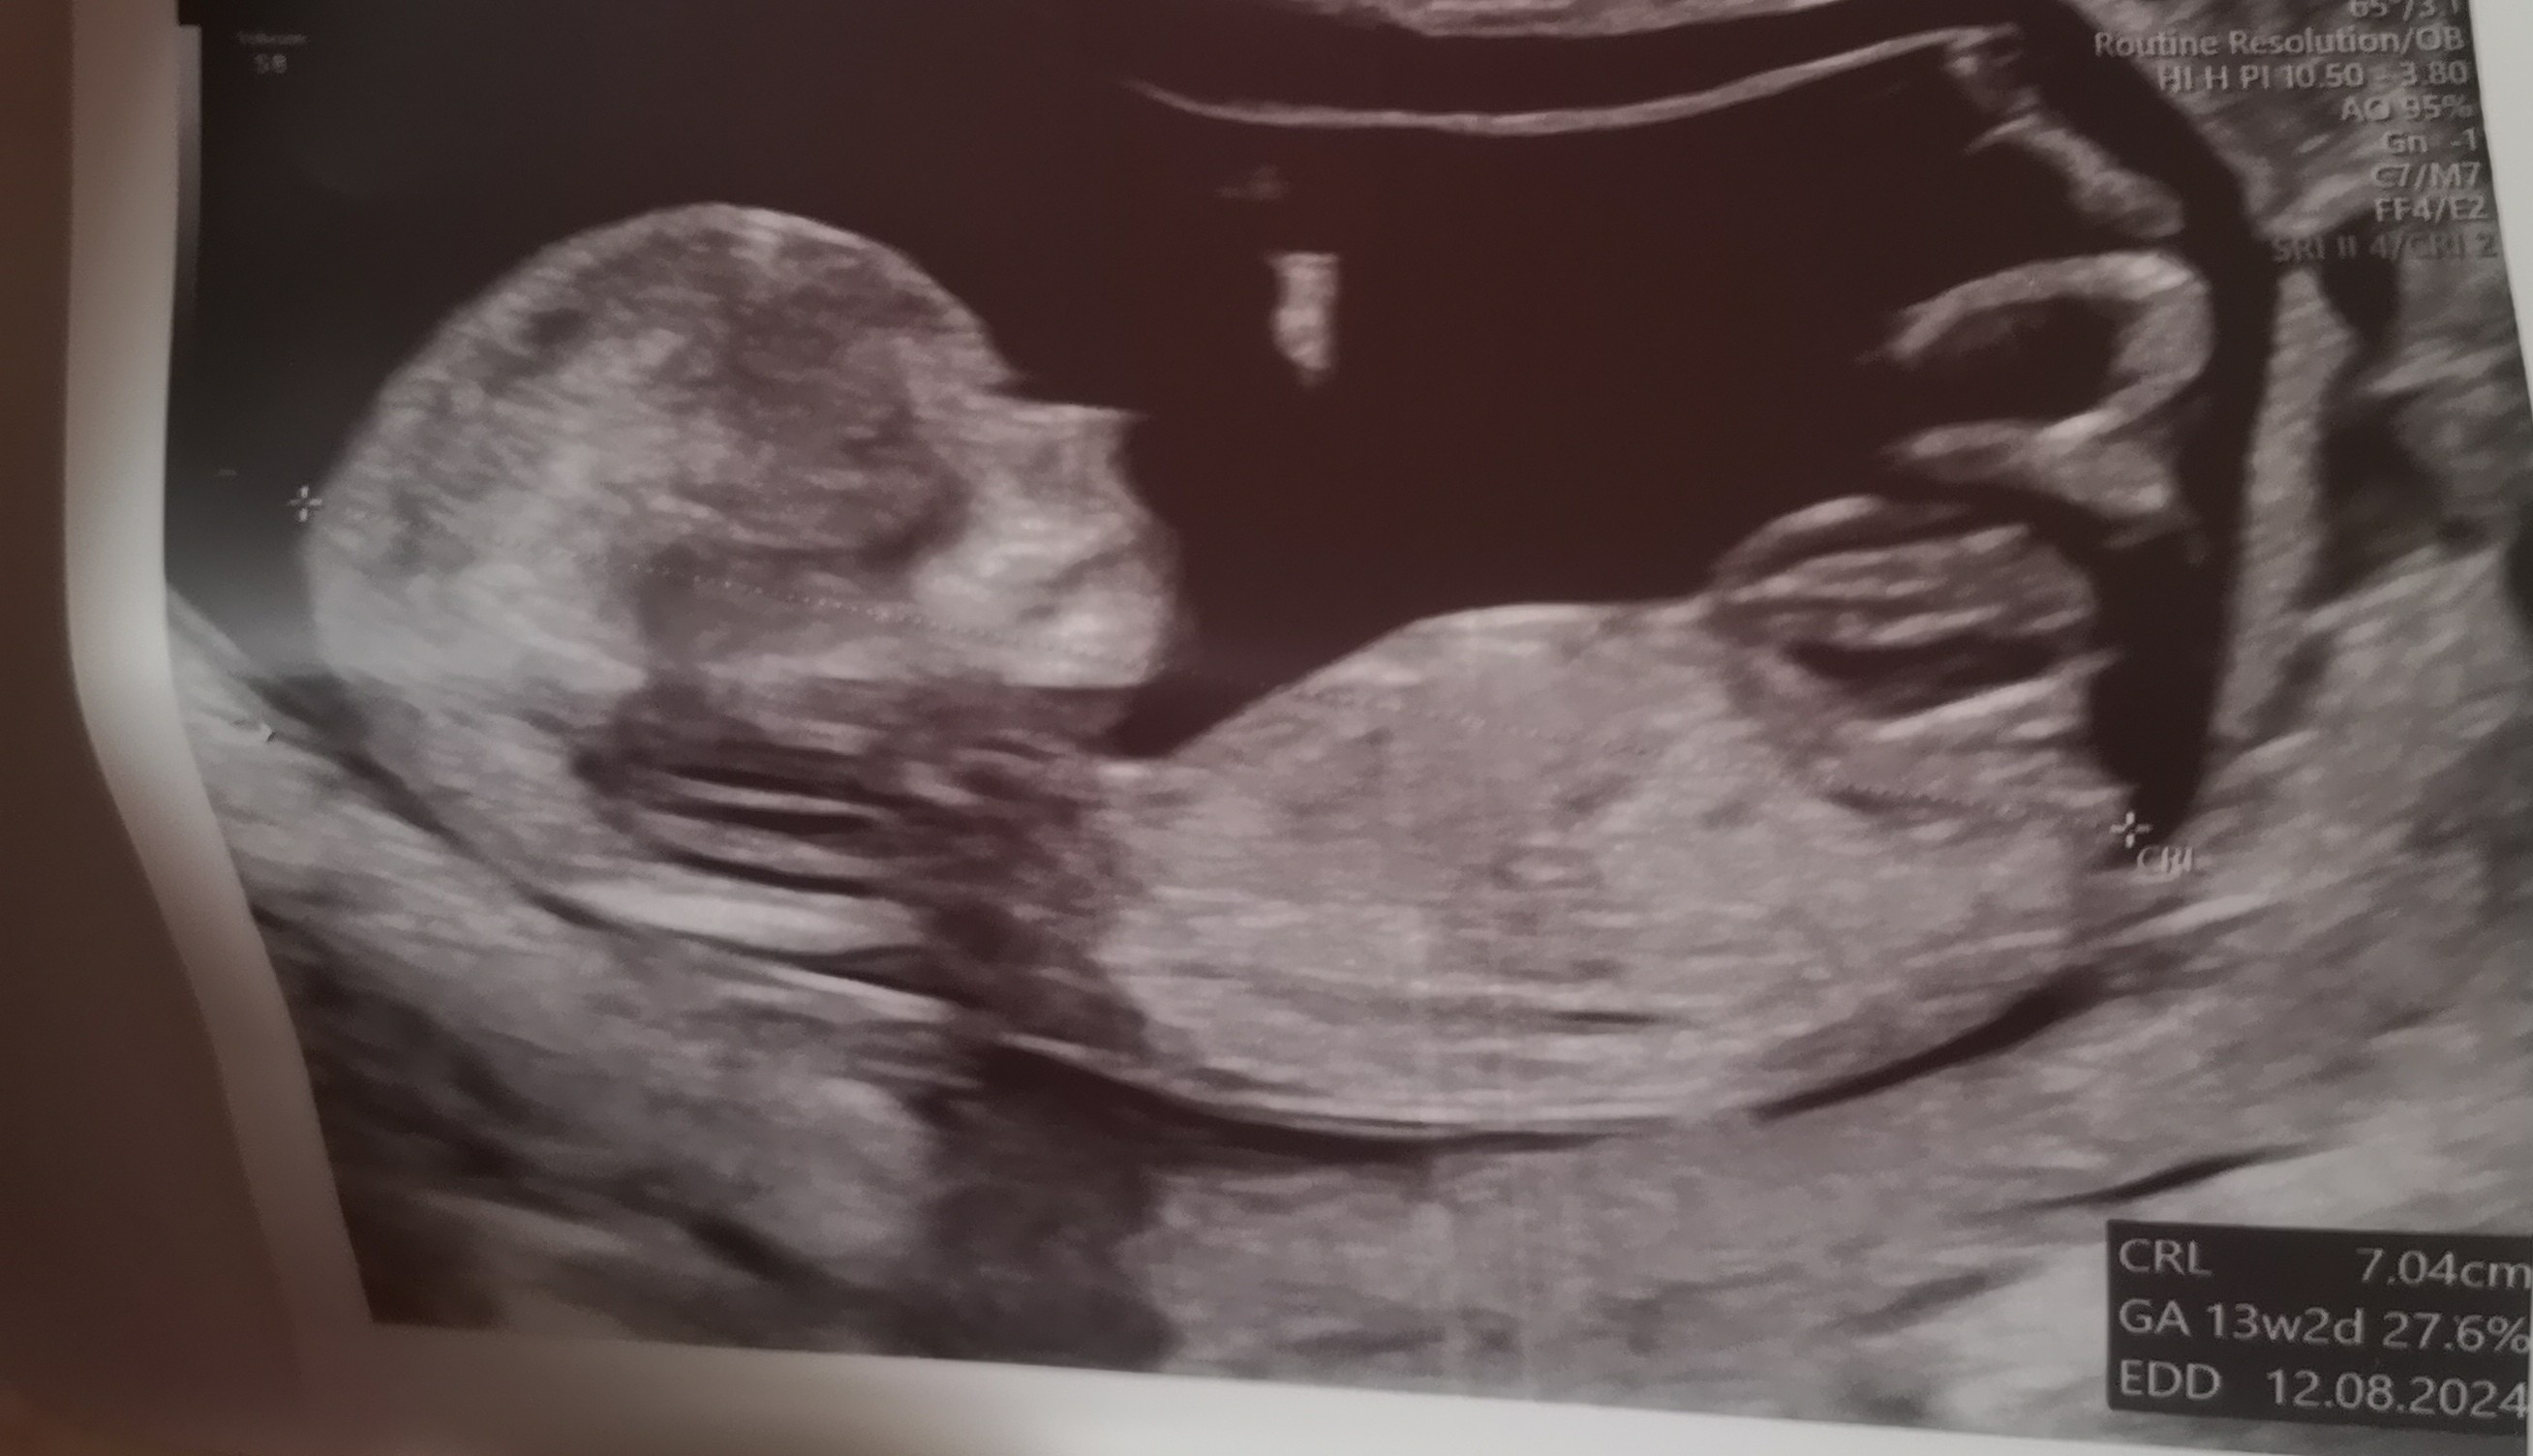

Z ostatniego USG mam tylko takie, chłopiec czy dziewczynka? ;)

Załączniki

• IMG_6255.jpeg

IMG_6255.jpeg

2,2 MB · Wyświetleń: 114